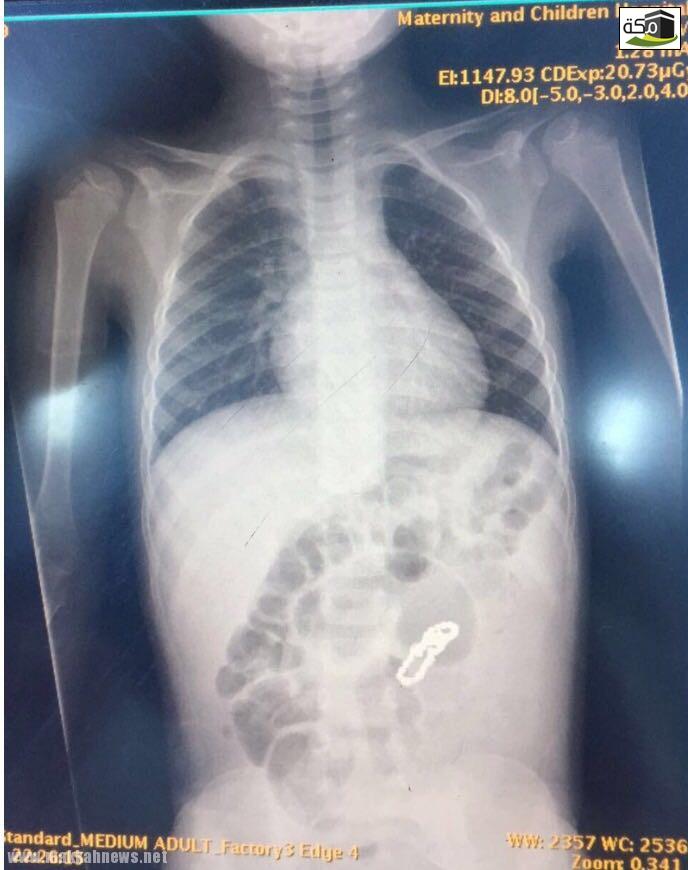

وأتضح من خلال الأشعة التي أجريت له في أحد المستشفيات الخاصة سابقاً وجود جسم غريب يشبه القطع المعدنية الشبكية في البطن.

وعلى الفور تم إجراء عملية جراحية استكشافية إثر حالته، واكتشف الفريق الطبي وجود ثقوب في الأمعاء الدقيقة وناصور بين أجزاء الأمعاء المتلاصقة نتيجة بلع القطع المغناطيسية، مما أدى إلى ثقوب في الأمعاء وأجري للطفل قص الأجزاء المثقوبة وتوصيلها ويتمتع الطفل حالياً بحالة صحية مستقرة.